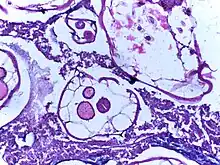

_(15806559973).jpg.webp)

.jpg.webp)

If complications of helminthiasis, such as intestinal obstruction occur, emergency surgery may be required.[9][56] Patients who require non-emergency surgery, for instance for removal of worms from the biliary tree, can be pre-treated with the anthelmintic drug albendazole.[9]